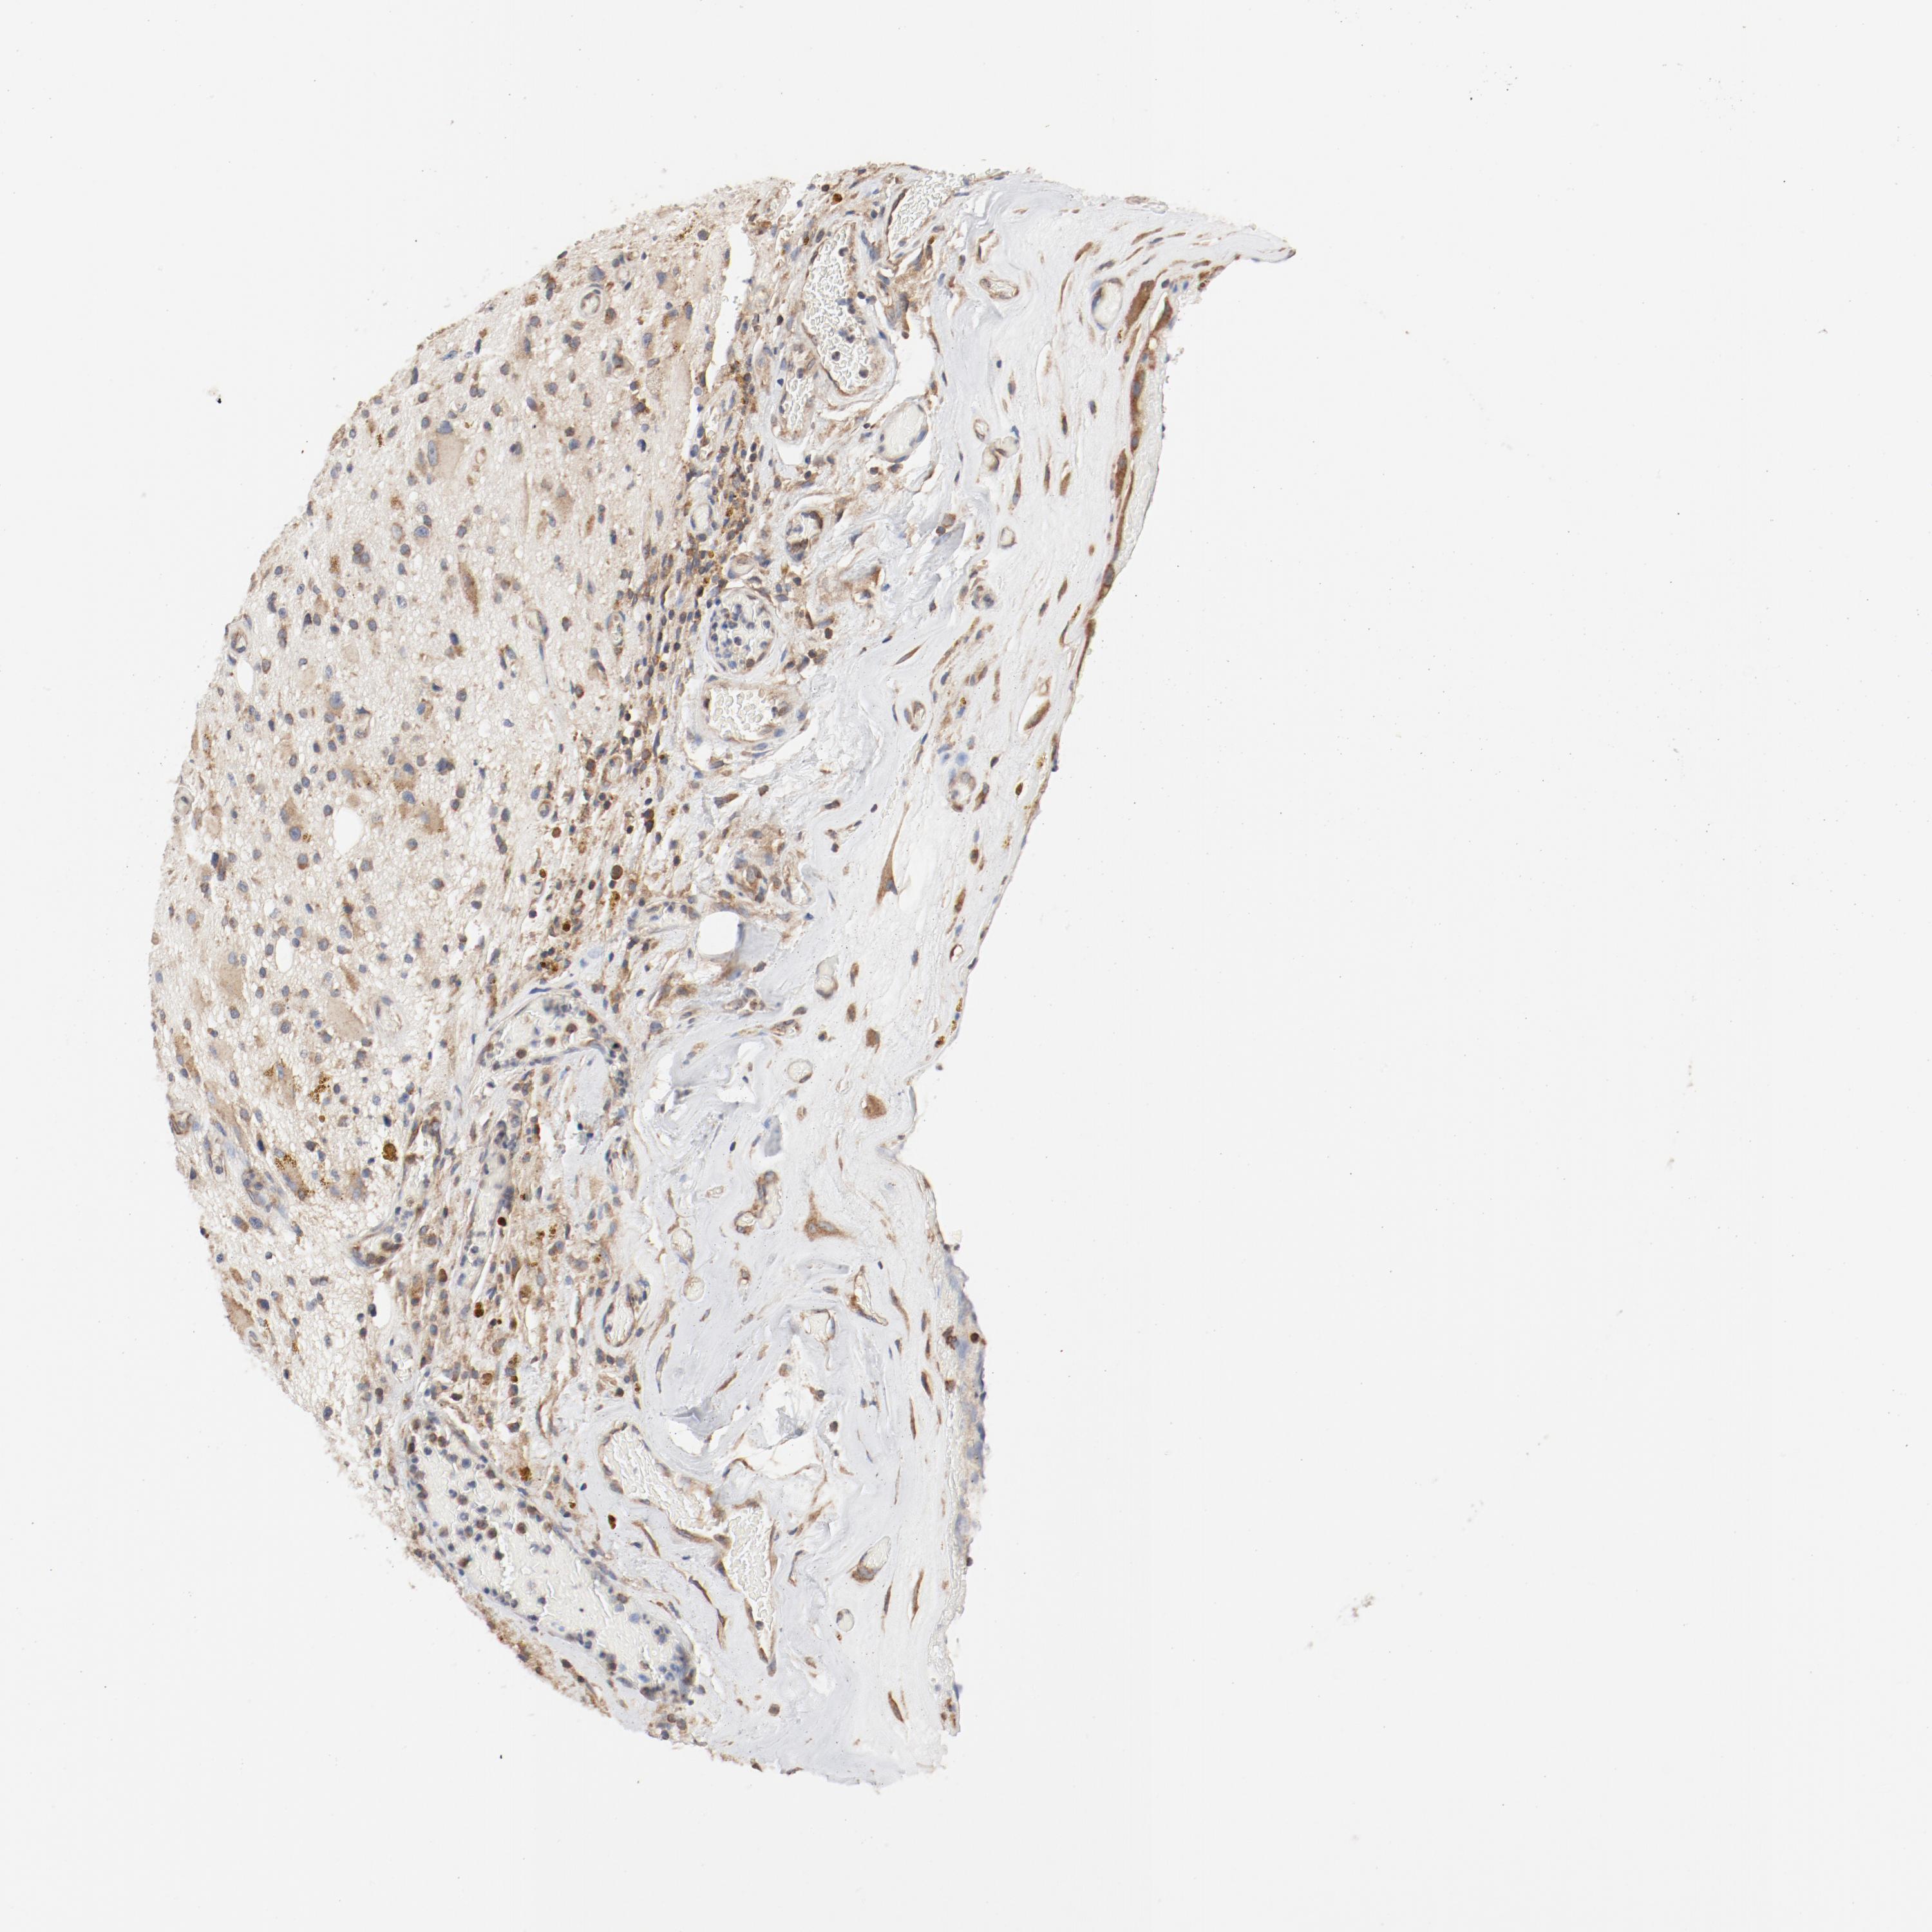

GLIOMA - Protein expressioni

A mouse-over function shows sample information and annotation data. Click on an image to view it in a full screen mode. Samples can be filtered based on level of antibody staining by selecting one or several of the following categories: high, medium, low and not detected. The assay and annotation is described here.

Note that samples used for immunohistochemistry by the Human Protein Atlas do not correspond to samples in the TCGA dataset.

Antibody stainingi

Antibody staining in the annotated cell types in the current human tissue is reported as not detected, low, medium, or high, based on conventional immunohistochemistry profiling in selected tissues. This score is based on the combination of the staining intensity and fraction of stained cells.

Each image is clickable and will lead to virtual microscopy that enables deeper exploration of all samples and also displays staining intensity scores, fraction scores and subcellular localization as well as patient and tissue information for each sample.

Antibody HPA031153

Antibody CAB004027

Glioma, malignant, High grade

Glioma, malignant, Low grade

Glioblastoma, NOS

Glioma, malignant, NOS